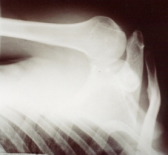

Foto 1 |

Después de un diagnóstico correcto de la LRH traumática y descartadas las fracturas o laxitud ligamentaria, el paciente es colocado en posición semisentada al borde de la mesa quirúrgica con el miembro superior libre y bajo anestesia general. Se practica la incisión anterior de más o menos 10 cm siguiendo las líneas del langer (Foto 1)